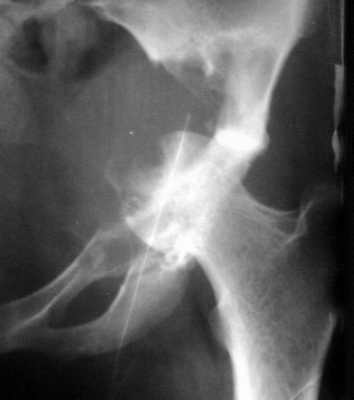

Остеобластокластома вертлужной впадины

Женщина 22 лет поступила с протрузией вертлужной впадины. Рентгенограммы (1, 2) с интервалом в 1 год. В онкодиспансере сделали биопсию - ОБК без малигнизации. Какой объем операции здесь следует предпринять? Есть ли какие-то шансы на первичное эндопротезирование? Где такие операции делают? В том числе в Европе. Заранее спасибо.